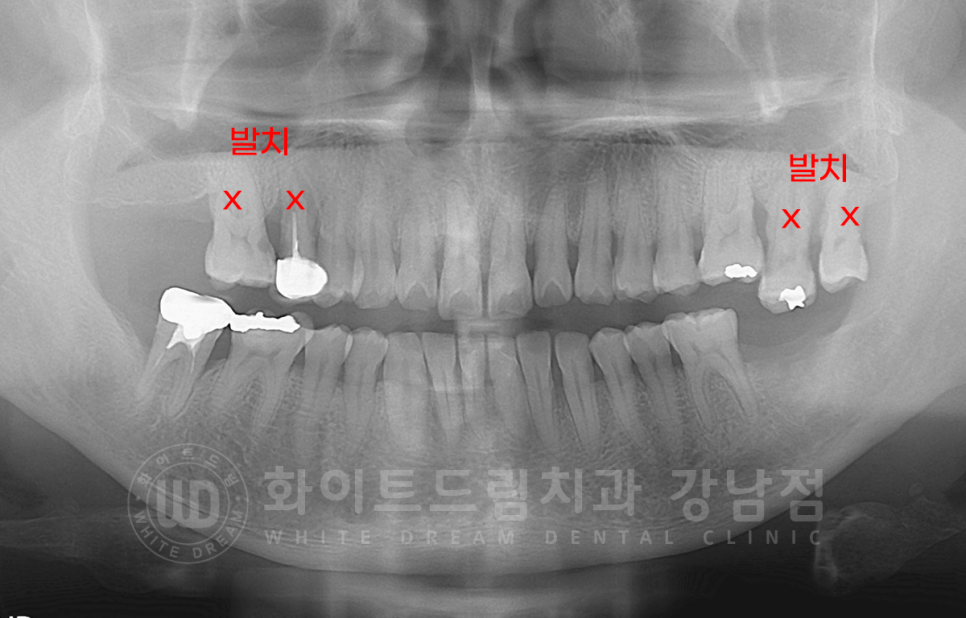

한 번에 모든 수술을 진행하면 식사가 어렵기 때문에 20번. 30번대 먼저 수술을 진행한 후

3개월 뒤 10번대 임플란트 수술을 진행하기로 했습니다.

20번대 발치 후 x-ray입니다.

잇몸뼈가 심각하게 없는 편은 아니었지만, 임플란트가 식립되기에는 측면 & 수직 잇몸뼈가 조금 부족한 상태였기에

crestal 방식의 상악동 거상술을 동반한 뼈이식과 임플란트 식립을 진행했습니다.